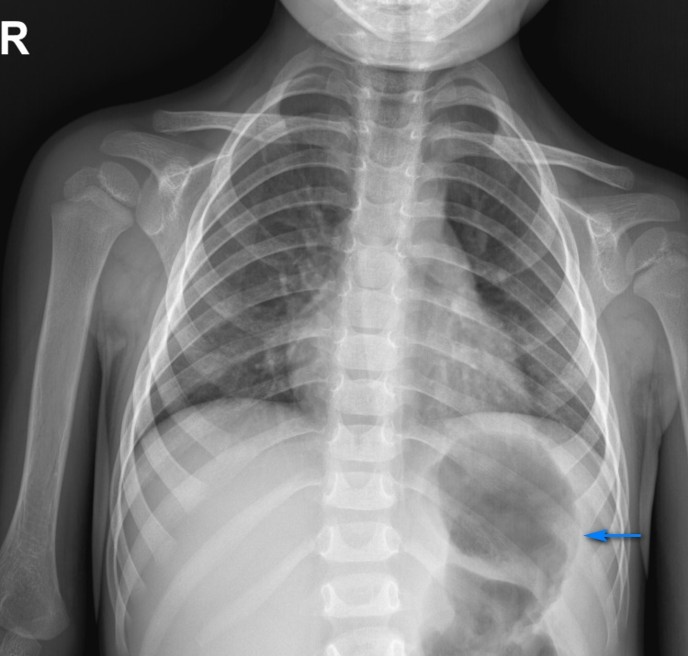

Chest radiography demonstrated an air filled structure with fluid in the left hemithorax and a significant mediastinal shift (Fig. 1a). Initially it was interpreted as hydropneumothorax and the child was admitted to the intensive care unit for thoracocentesis. Gastric gas was not seen in the left upper abdomen after careful observation of the chest X-ray, so the decision was made to insert a nasogastric tube (NGT) which led to the resolution of respiratory symptoms. That directed us to the assumption of potential tension gastrothorax (Fig. 1b). In line with this, the patient was further evaluated by a computerized tomography (CT).

In the case of tension pneumothorax, the gastric air is seen under the left hemidiaphragm which is well-defined and depressed. The parenchyma of the left lung is medially compressed. On the other hand, the left hemidiaphragm is poorly defined in the case of gastrothorax and a gastric bubble is not seen in the left upper quadrant of the abdomen. Superior margin of the air filled structure is formed by the compressed lung parenchyma and the stomach wall.7